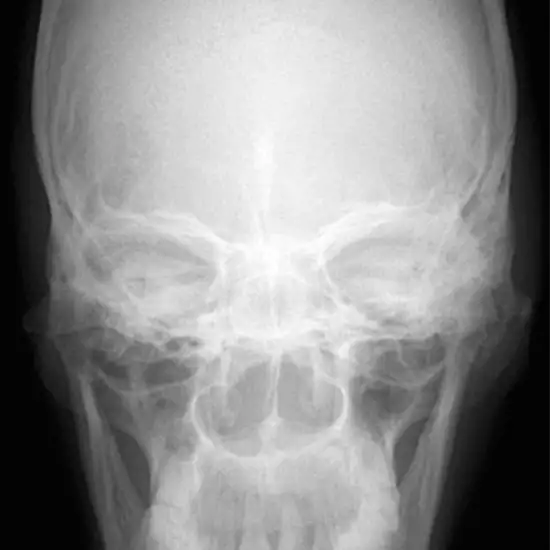

X-Ray Maxilla AP View

What is an X-ray Maxilla AP View Test?

The jaw is made up of a bone called the maxilla. An X-ray called a Maxilla AP View (upper jaw) looks at the maxillary bones. At the midline and in the middle of the face, the two maxillary bones meet on either side of the face.